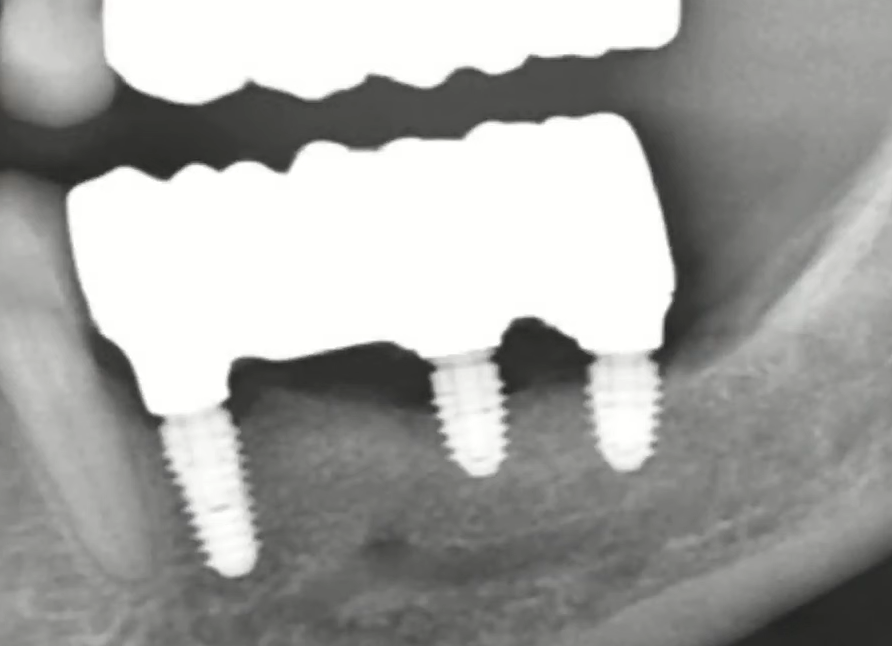

Conversely, there are examples of poor implant selection. The image shows cortical conical implants designed for a ridge-splitting protocol. They were placed in dense bone, but due to excessive pressure at the implant neck, significant bone volume was lost even before the healing abutments were placed. Now they need to be removed, the implant site remodeled, and new implants placed.

Significant bone loss during implant placement due to a design error; implants designed for the ridge-splitting technique were placed into the bone without splitting. YouTube / Dr. Kamil Khabiev / Dental Guru Academy